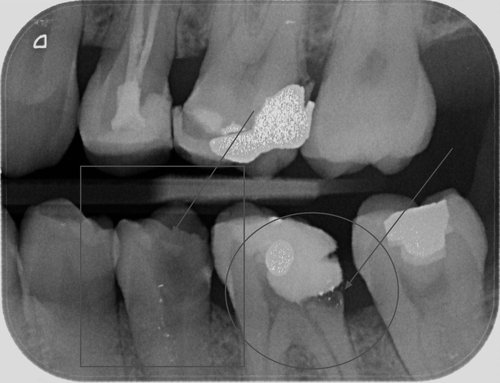

Obr. 2 Nápadné „váčky“ u kořenů pravé dolní šestky, tedy chronický bakteriální zánět v kosti.

Bakterie tak mohou volně proudit z úst do kosti. Obvyklý vývoj neošetřeného nebo nedokonale ošetřeného kazu je prostup bakterií do prostoru dřeňové dutiny. Počáteční dlouhodobá citlivost na chlad a sladké se změní v pulzující špatně ztišitelnou bolest, která budí pacienta ze spaní. Už v této chvíli je vlastně pozdě a zubní lékař by měl ošetřit kořenové kanálky a zamezit bakteriím v šíření hlouběji do zubu. Nestane-li se tak, šíří se infekce kořenovými kanálky dál hlouběji směrem do čelistní kosti. V tuto chvíli se dostaví výrazná bolest na skus. A jsme opět na křižovatce. Tělo buď zánět převede do chronicity a vytvoří se obávaný váček prostupující všechny internetové diskuze pod zubařskými články, nebo infekce pokračuje akutně dál. Člověka sužují kruté bolesti z rozvíjejícího se abscesu, což není nic jiného, než jezero hnisu. Absces se může provalit do úst, což je sice krajně nechutné, ale přinese to aspoň částečnou úlevu. Pokud se ale hnisavý zánět šíří štěrbinovitými anatomickými komunikacemi dál, nastává problém. Infekce může v závislosti na příčinném zubu směřovat do oka, do mozku, do plic nebo srdce. Vůbec nejhorší jsou extrémně rychle probíhající infekce, kdy se hnis ani nestihne vytvořit a člověk navzdory antibiotikům a intenzivní péči umírá na selhání orgánů při sepsi nebo i udušení z otoku dýchacích cest. Léčba takovýchto stavů je i dnes velmi obtížná a často vyžaduje rozsáhlé chirurgické zákroky.